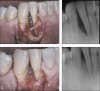

Figure 4  Severe bone defect extending nearly to the tooth root apex (4A and 4B) treated with rhPDGF and mineralized bone allograft. Surgical reentry and radiograph 11 months later shows nearly complete bone fill (4C and 4D).

Figure 4